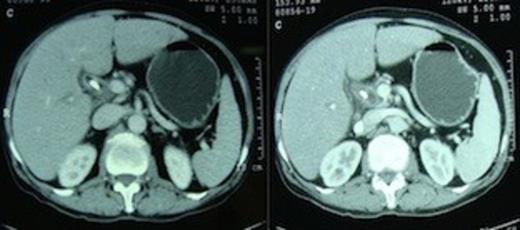

A 55 year non-diabetic male with painless progressive jaundice, pruritus and weight loss of 3 month duration was admitted in emergency with cholangitis. Investigations revealed a total leukocyte count of 17 000/cu.mm, total bilirubin: 222.3 μmol/L, direct: 136.8 μmol/L and alkaline phosphatase level: 1153 U/L. Side viewing endoscopy showed an ulceronodular growth at papilla, a papillotomy and endoscopic biliary plastic stenting was done. Neither cholangiogram nor pancreaticogram was obtained in view of cholangitis. Once his cholangitis resolved, he was referred for surgery. Pre-operative triple phase CT (computed tomography) scan of the abdomen showed a resectable ill-defined hypodense mass in the region of ampulla, the pancreatic head and uncinate were normal however the neck, body and tail of pancreas were absent (figure 1,2).

Computed tomography scan demonstrating absence of the body and tail of pancreas anterior to the splenic artery and vein.